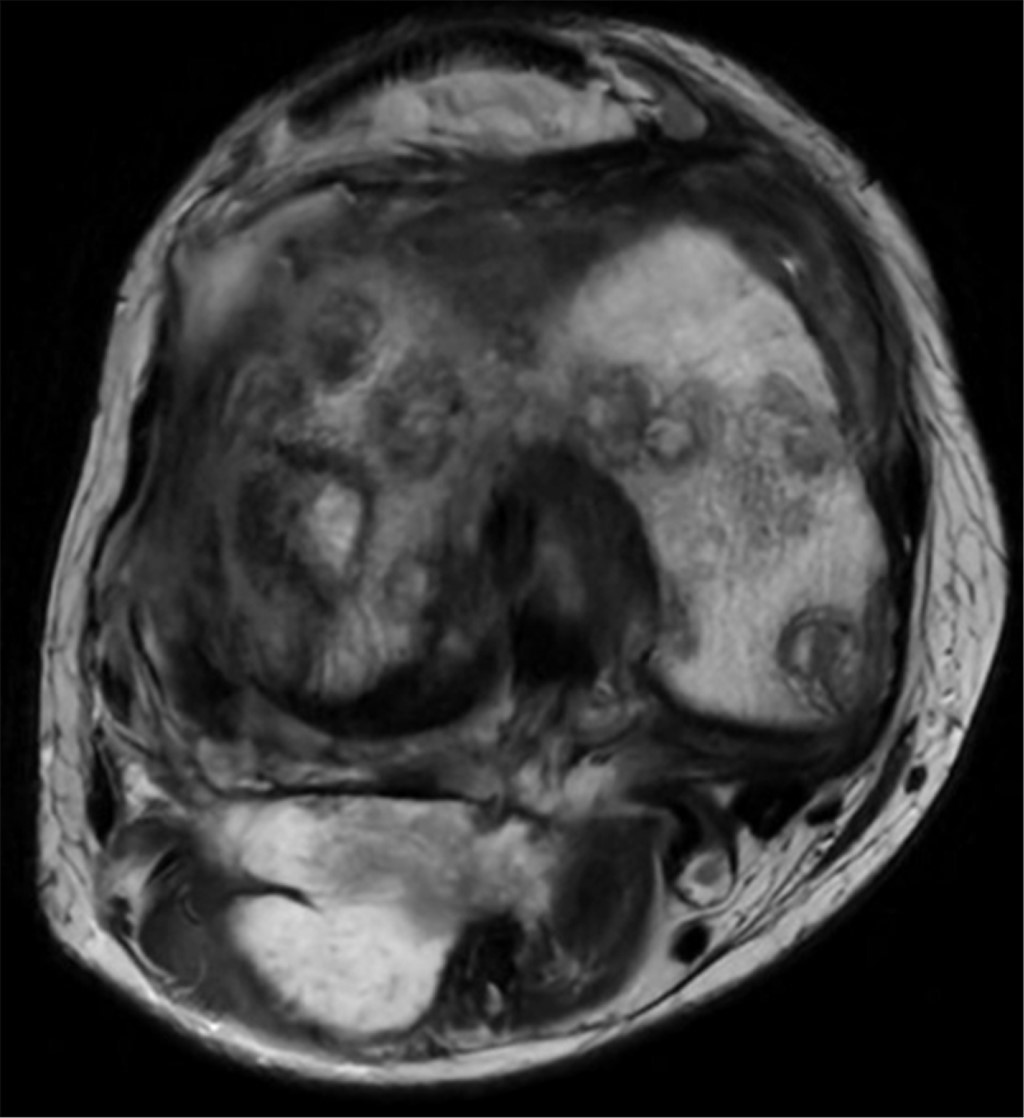

Candida glabrata osteomyelitis with septic arthritis in right knee

osteomyelitis, Candida glabrata, Baker\'s cyst, septic arthritis.

Osteomyelitis caused by Candida glabrata is an uncommon pathology that can cause severe complications if not detected and treated opportunely; it represents a diagnostic and therapeutic challenge due to the scarce reported information. We present the case of a 57-year-old woman with long-term, uncontrolled type 2 diabetes who presents osteomyelitis and septic arthritis caused by C. glabrata in the right knee after a direct trauma that later required three surgical interventions without remission. We describe the diagnostic methodology and evolution of the case during the patient's hospital stay.

Figure 1